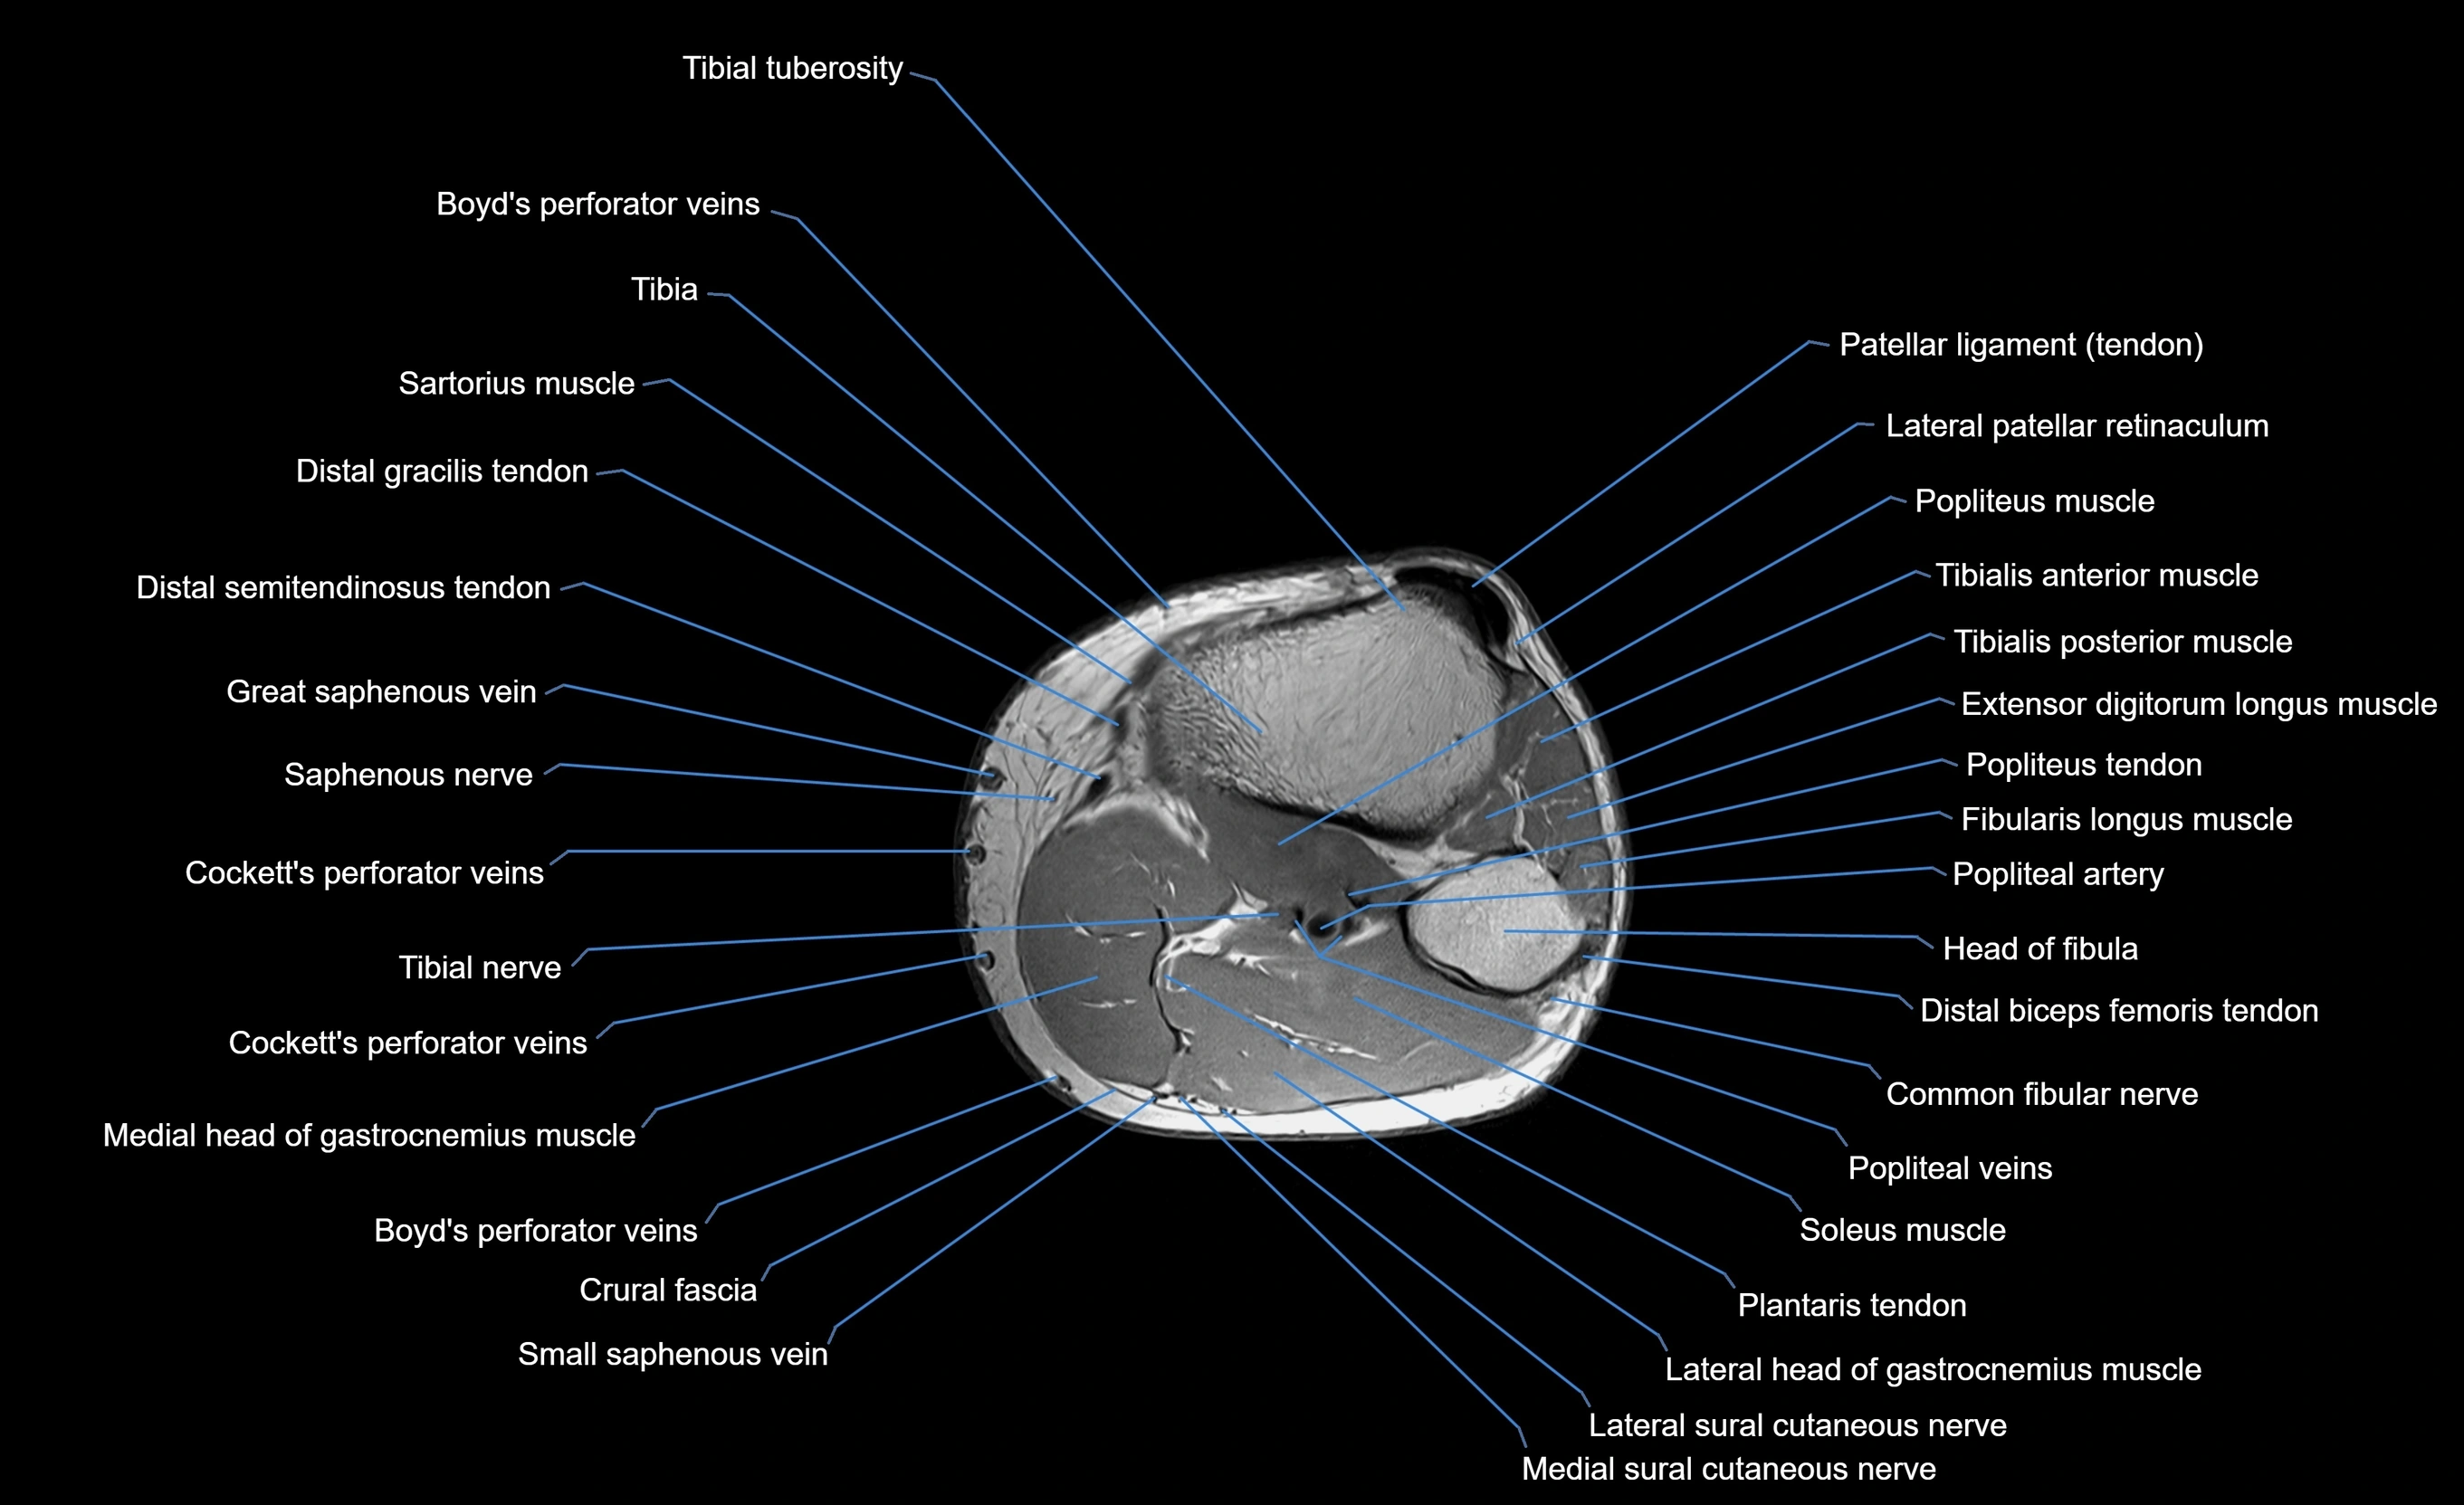

MRI image